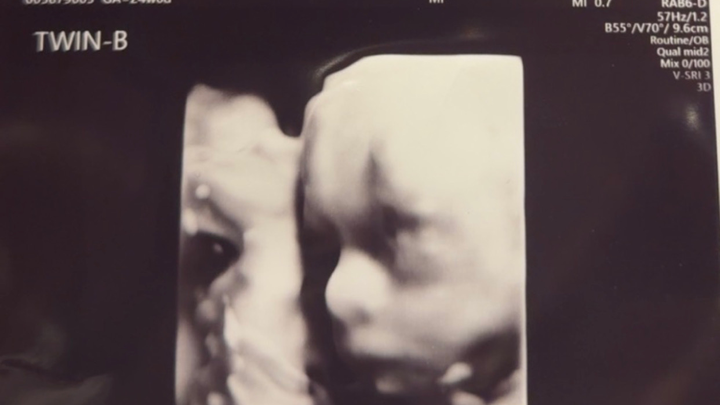

On January 5th, my sister Beverly & her fiancé Cotton received news they weren't prepared for at all.... she is currently 25 weeks pregnant with TWIN BOYS. A little back story, Florence OB sent her to Charleston last week to see a more high-risk doctor because of BABY B not gaining weight, not getting enough oxygen or blood supply, they wanted to admit her last Wednesday and take the boys that Friday, being a first time mom she didn't consent she came home and did steroid shots Thursday and Friday along with a follow today that came with the solution of admitting her on Wednesday and monitoring the boys every 3 hours for the next 2 weeks and taking them at 27 weeks as long as they don't start to decline in any form. With that being said she will be out of work for 8 weeks total and Cotton will be the only income they have for the 8 weeks and traveling back and forth from work and home to see his fiancé and babies. Donations will be used for travel expenses, food and everyday living.